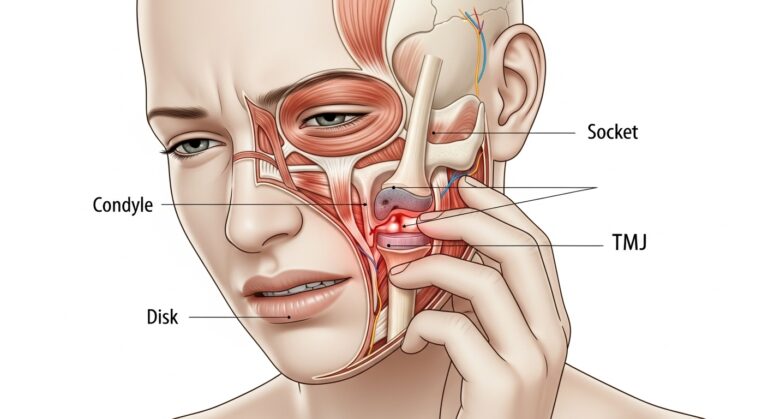

What Is It? Temporomandibular disorders (TMDs) describe several problems that affect your temporomandibular joint (TMJ), or jaw joint, and the muscles…